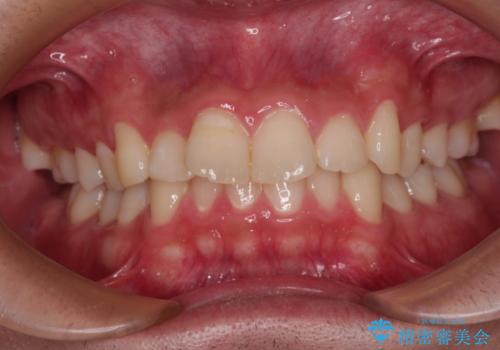

捻れて前に出ている前歯 ワイヤー装置での非抜歯矯正